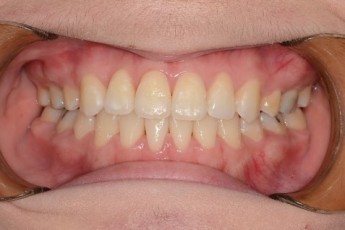

BEFORE & AFTER